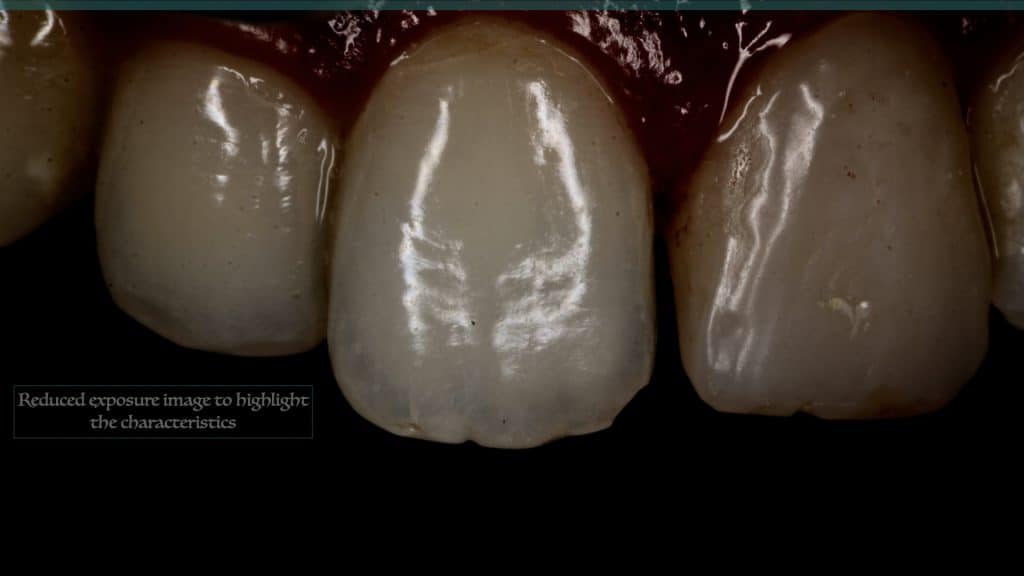

20 days post-op after suture removal